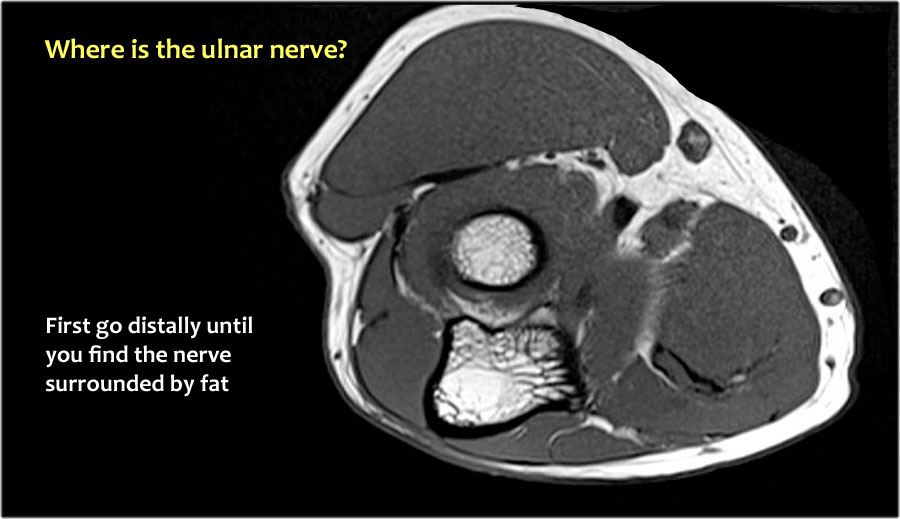

Vì vậy, khi chúng ta quay lại hình ảnh, bạn sẽ nhận thấy rằng có thể khó tìm thấy dây thần kinh.

Bất kỳ cấu trúc dưới da nào trong số này đều có thể là dây thần kinh đã được chuyển vị.

Một cách để thực hiện là đi theo các cấu trúc về phía xa cho đến khi tìm thấy dây thần kinh trụ ở phía xa tại vị trí bình thường của nó ở vùng cẳng tay gần được bao quanh bởi mô mỡ.

Sau đó khi bạn theo dõi nó về phía gần, bạn sẽ nhận thấy rằng đây là một trường hợp chuyển vị dưới da.

Trong trường hợp này, có viêm dây thần kinh.

Có sự phì đại của dây thần kinh.

Trên hình ảnh T2W có tín hiệu cao.

Dấu hiệu khác là sự phì đại không đồng đều của các bó sợi thần kinh, được thấy trên hình ảnh mặt phẳng đứng dọc (mũi tên).